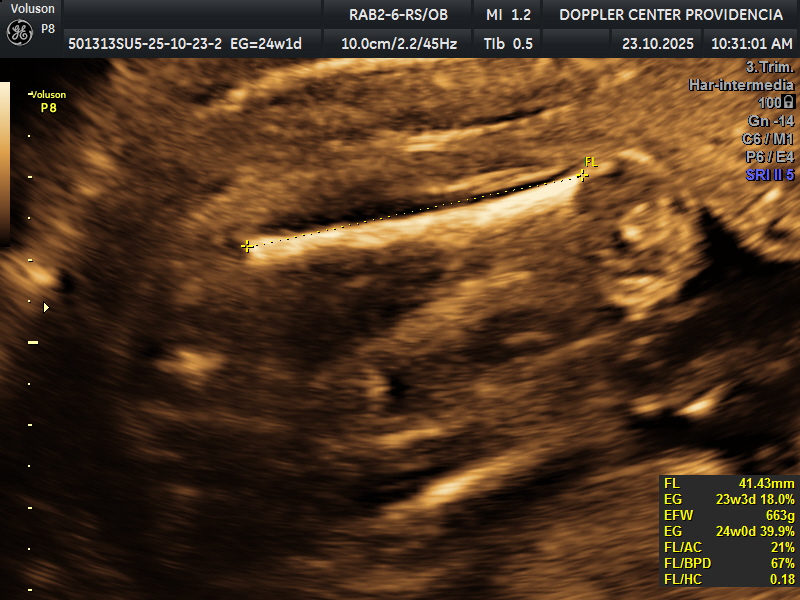

• Eco Doppler 22-24 semanas